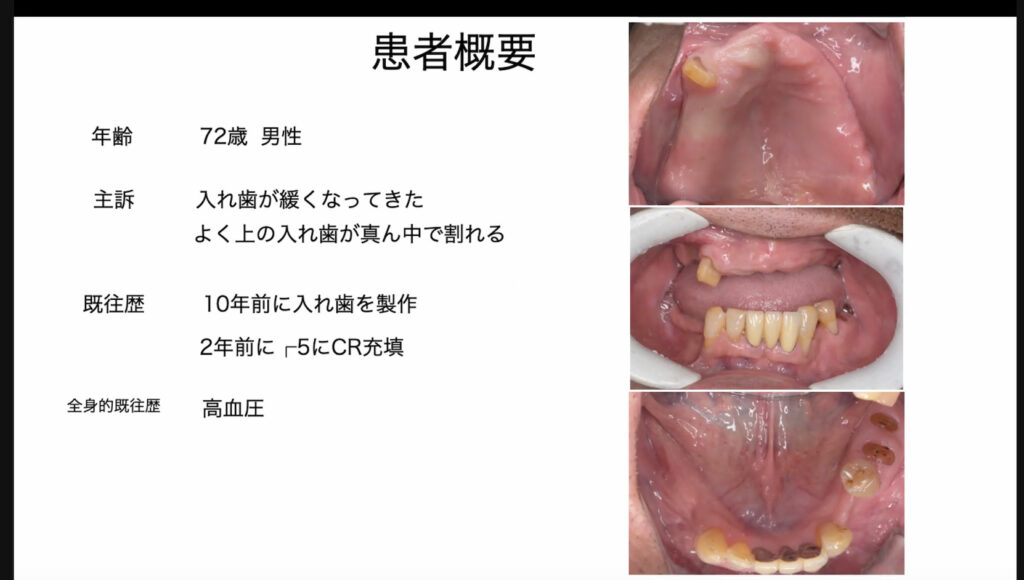

内容は、骨造成を伴うインプラント治療についてです。実際発表することにより、プレゼンスライドの不足に気づくのでいい機会になりました。

内容は、骨造成を伴うインプラント治療についてです。実際発表することにより、プレゼンスライドの不足に気づくのでいい機会になりました。